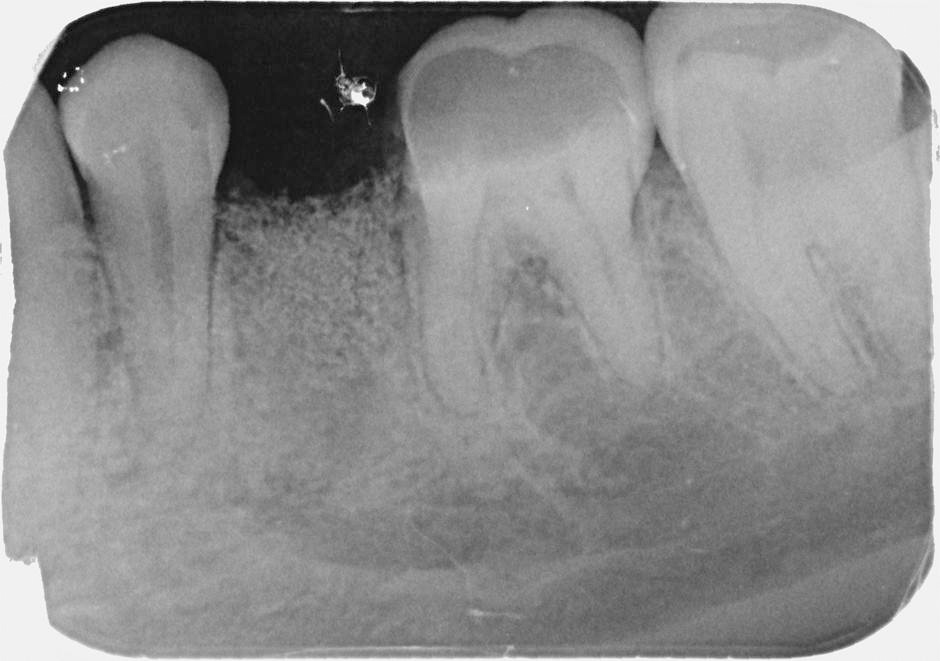

Jedná se o vyzvednutí membrány, která čelistní dutinu vystýlá, pod vyzvednutou membránou vznikne kapsa, kam se umístí augmentační materiál, do kterého se zavedou implantáty.

Vhojení implantátů se při této operaci prodlužuje na 6-12 měsíců.